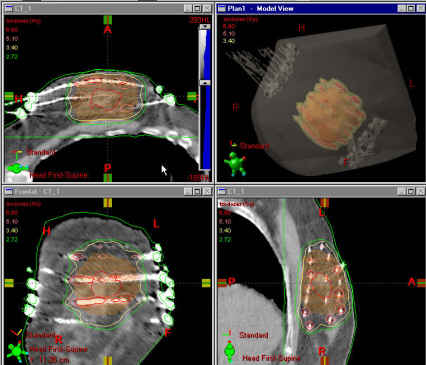

Both permanent and temporary prostate implants are available to our patients. Permanent implants (low dose rate, or LDR) involve the placement of many tiny radioactive seeds into the prostate gland under ultrasound. These implants are done in a single session. For temporary implants (high dose rate, or HDR), hollow catheters are placed into the prostate. A high-activity radioactive source is then fed under computer-control into each catheter and then removed. Temporary implants often can be done in one or two sessions. Both LDR and HDR implants can be done as the sole treatment for prostate cancer, or in some circumstances, in combination with external beam radiation.

Photo: A radiation treatment plan for permanent prostate seed brachytherapy.

Photo: A three-dimensional rendering of seed positions for permanent prostate brachytherapy.